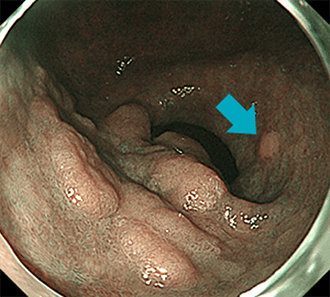

春間-川口病変では、NBI観察で顕在化して視認性が上がることが多いです。腫瘍性ポリープには、良性の胃腺腫、悪性の胃がんが含まれます。胃腺腫は粘膜上皮が腫瘍化しているものの、悪性化はしておらず良性のものを指します。長期間変化がなく経過するものもありますが、がん化することがまれではありません。

胃腺腫胃カメラ(胃内視鏡検査)の施行時に、偶然みつかることがほとんどです。健診・胃がん検診でのバリウム検査が、発見契機になることも多いです。胃底腺ポリープや過形成ポリープのほとんどは、内視鏡観察での鑑別が可能です。胃底腺ポリープは周囲粘膜と同じ色調の、つるつるとした無茎性~亜有茎性の数mm程度のことが多い病変です。対して過形成ポリープは赤みの強いやや凹凸のある表面をした、亜有茎性~有茎性のこともあるポリープです。胃底腺ポリープではがん化は非常にまれで、過形成ポリープでも通常は2cmを超えない場合での担がんは比較的まれです。しかしながら小さくても形態からラズベリー様腺窩上皮型胃腫瘍(ラズベリー型胃がん)との鑑別を要すことがあります。そのため通常は胃底腺ポリープ・過形成ポリープでは生検での組織病理学的検査を要することは少ないですが、上記のような場合や、家族性大腸腺腫症(FAP)に生じる胃底腺ポリープなどではがん化していないかをみるために、生検を要することがあります。

比較的大きな病変であっても、胃がんでなく腺腫であることもあります。

NBI観察で、上記病変の近傍の小さな別病変が明瞭化しています。また胃腺腫の場合はがん化する確率が高く、また高分化型がんを見た目だけで否定することは難しいため、発見時には原則生検が施行されます。さらに胃腺腫で治療しない場合においては、がん化リスクがあることから定期的な胃カメラ検査は必須となります。